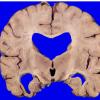

11B1 Pick Dz & ADNC (Case 11)_1

11B2 Pick Dz & ADNC (Case 11)_2

11B3 Pick Dz & ADNC (Case 11)_3

11B4 Pick Dz & ADNC (Case 11)_4

11B5 Pick Dz & ADNC (Case 11)_5

11B6 Pick Dz & ADNC (Case 11)_7

11B7 Pick Dz & ADNC (Case 11)_9

11B8 Pick Dz & ADNC (Case 11)_14